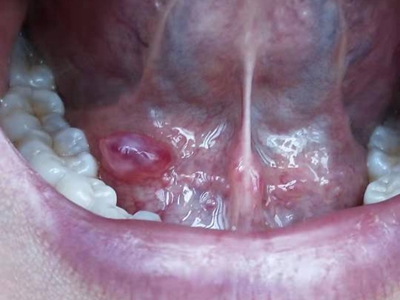

舌下腺囊肿口腔舌系带处有肿起的圆疙瘩图

舌下腺囊肿患者皮损为舌系带处透明带点红色的圆疙瘩样囊肿,局部触之有波动感,质地柔软而有弹性,但囊肿变大后可影响进食与发音。